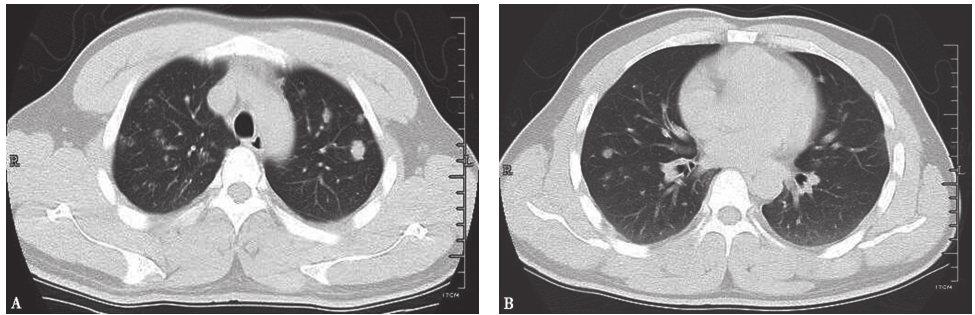

胸部CT:两肺野内可见多发结节状、斑片状密度增高影,以两上肺为主,病灶形态欠规整,其内密度不均,部分内见空洞(图1)。

图1入院前胸部CT表现